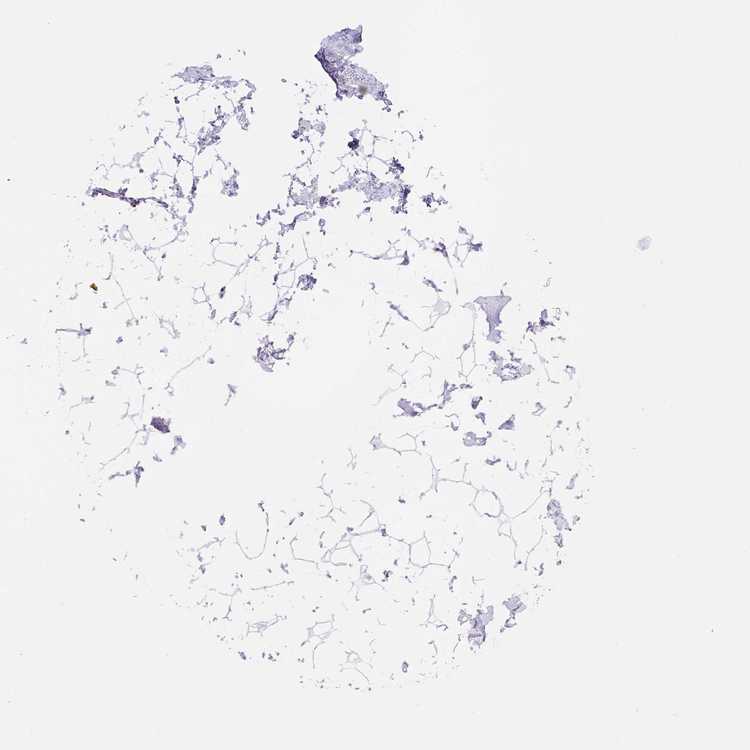

BREAST - Antibody stainingi

Antibody staining in the annotated cell types in the current human tissue is reported as not detected, low, medium, or high, based on conventional immunohistochemistry profiling in selected tissues. This score is based on the combination of the staining intensity and fraction of stained cells.

Each image is clickable and will lead to virtual microscopy that enables deeper exploration of all samples and also displays staining intensity scores, fraction scores and subcellular localization as well as patient and tissue information for each sample.

Antibody HPA067538

Adipocytes Not detected

Glandular cells Not detected

Myoepithelial cells Not detected